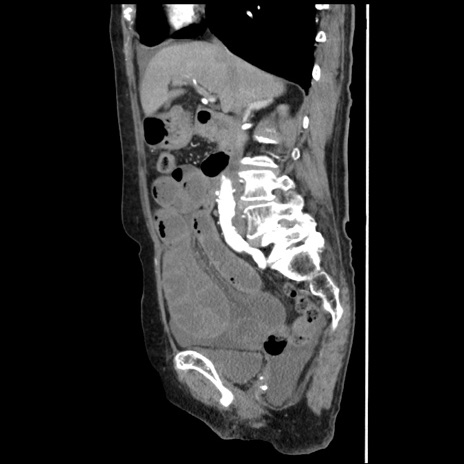

症例1(矢状断像)

【症例】80歳代女性

【主訴】腹痛

【現病歴】8時間前から腹痛あり来院。

【既往歴】糖尿病、脂質異常症、子宮体癌にて子宮全摘術

【身体所見】意識清明・会話良好だが腹痛で苦悶様、全腹部にわたって反跳痛と圧痛あり

【データ】WBC 13600、CRP 0.14、LDH 224、CK 90